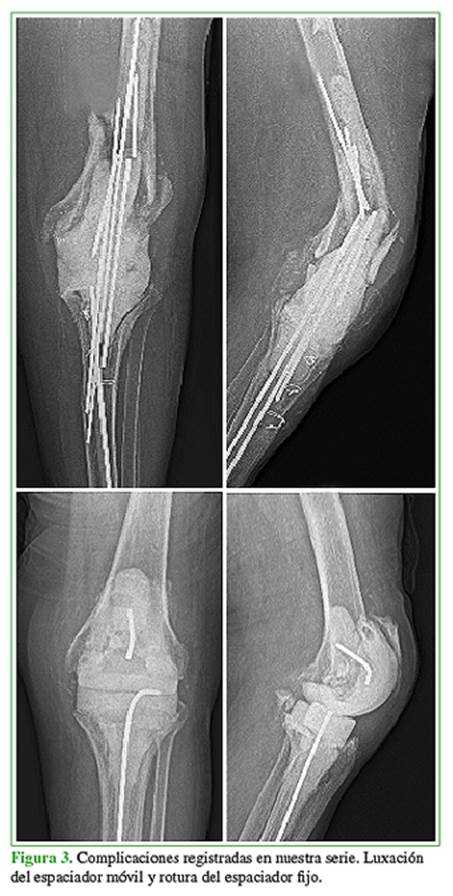

Por último, no se observaron diferencias en la frecuencia de complicaciones entre ambos grupos en cuanto a rotura o luxación del espaciador, reinfección o trombosis venosa profunda (Tabla 4, Figura 3).

Por último, las revisiones sistemáticas publicadas, como la de Voleti y cols., donde se analizan 1526 pacientes en estudios con nivel de evidencia III y IV, revelaron que no existen diferencias en las tasas de reinfección según el tipo de espaciador empleado (12% espaciadores fijos vs. 8% articulados, p 0,01).13,14 Nuestros resultados coinciden con esta afirmación; a su vez, no hubo diferencias significativas en las complicaciones relacionadas con el tipo de espaciador empleado entre ambos grupos.